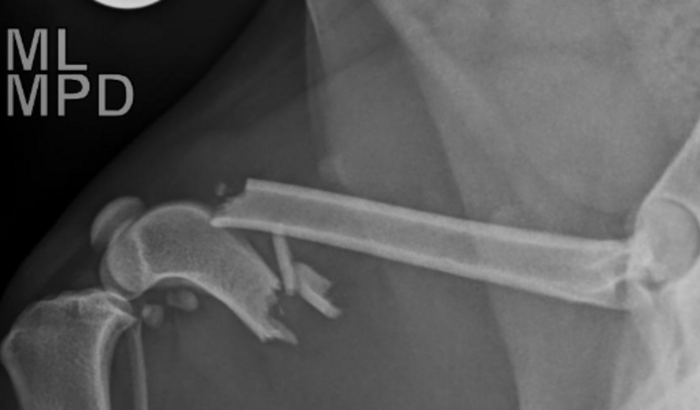

Em uma dessas minhas travessuras fugi das minhas mamães pulei o muro e fui para cima do telhado da vizinha e cai em uma altura de mais de 4 metros no barro quebrei o fêmur da pata direita e agora vou precisar de cirurgia urgente.